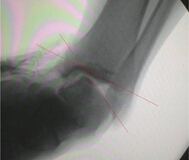

在外踝韧带损伤时,应力位摄片和磁共振(MRI)影像研究进展迅速,这为准确诊断和确定治疗方案创造了条件。应力位的摄片对于可靠地判断韧带是否断裂非常重要,尤其是慢性损伤,需要考虑行断裂韧带重建术时,我们应尽量完成此项检查。通常应力位检查包括:1判断距腓前韧带损伤的前抽屉试验(anterior drawer test),2判断距腓前韧带损伤的距骨倾斜试验(inversion talar tilt test)。前抽屉试验是固定踝关节近端,跖曲20°牵拉踝关节远端向前时,比较胫骨和距骨后缘与力线的距离(图4),距骨前移超过5 mm(与对侧比较)为可疑阳性,超过9 mm为阳性;van Dijk等证实该检查的敏感度73%,特异度97%。距骨倾斜试验是固定踝关节近端,对踝关节远端施以内翻应力,评估胫距关节面夹角(图5);评判标准:与对侧比较,大于5°为可疑阳性,超过10°为阳性;或者单侧超过15°为阳性。踝关节轻微跖曲时应力位查体比轻微背曲时,更容易获得阳性表现。当然非应力位下实施的常规X线片,例如踝关节正侧位、踝穴位、足正侧位等有助于排除踝关节骨折、力线异常、骨赘、局灶性骨坏死等需要鉴别诊断的疾病。踝关节磁共振(MRI)检查,对于判断踝关节韧带损伤具有重要价值,韧带结构在T1和T2相呈低信号,韧带断裂表现为韧带结构连续性中断,或者正常低信号结构消失。为了清楚显示ATFL结构,需要采用斜横断位扫描才能显示ATFL全长,此时舟骨恰呈“哑铃状”(图6)。踝关节三维CT检查,不是踝关节韧带损伤的常规检查,但是对判断外踝小骨块是哪根韧带的撕脱性骨折,还是游离体,或者是腓骨肌腱的籽骨,具有重要的参考价值,这对于完善术前治疗方案有较大帮助。

5A

5B

A:操作手法;B:X线片示阳性,红线代表胫距关节面夹角

图5 左踝距骨倾斜试验